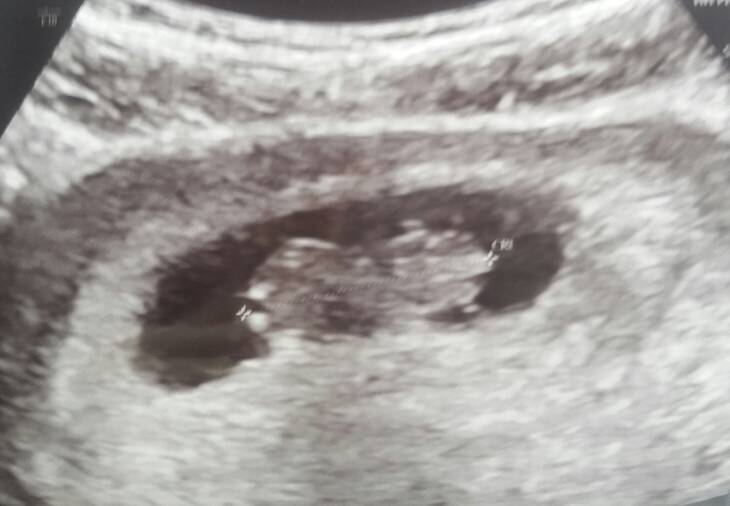

Czy któraś już w okolicach 12 tc miała robione USG przez brzuch? Bo mąż chciałby iść że mną a jednak wolałabym żeby Usg było wtedy przez brzuch